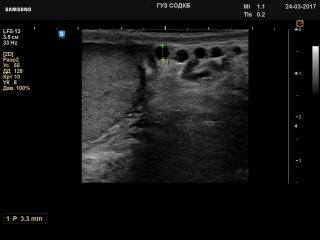

Atlas of ultrasound images - urology

In the section "Urology" of atlas the results of ultrasound examinations of male maladies are represented. Here you can see images of the bladder, prostate, etc. Echography of the kidneys find at "Abdominal examinations".